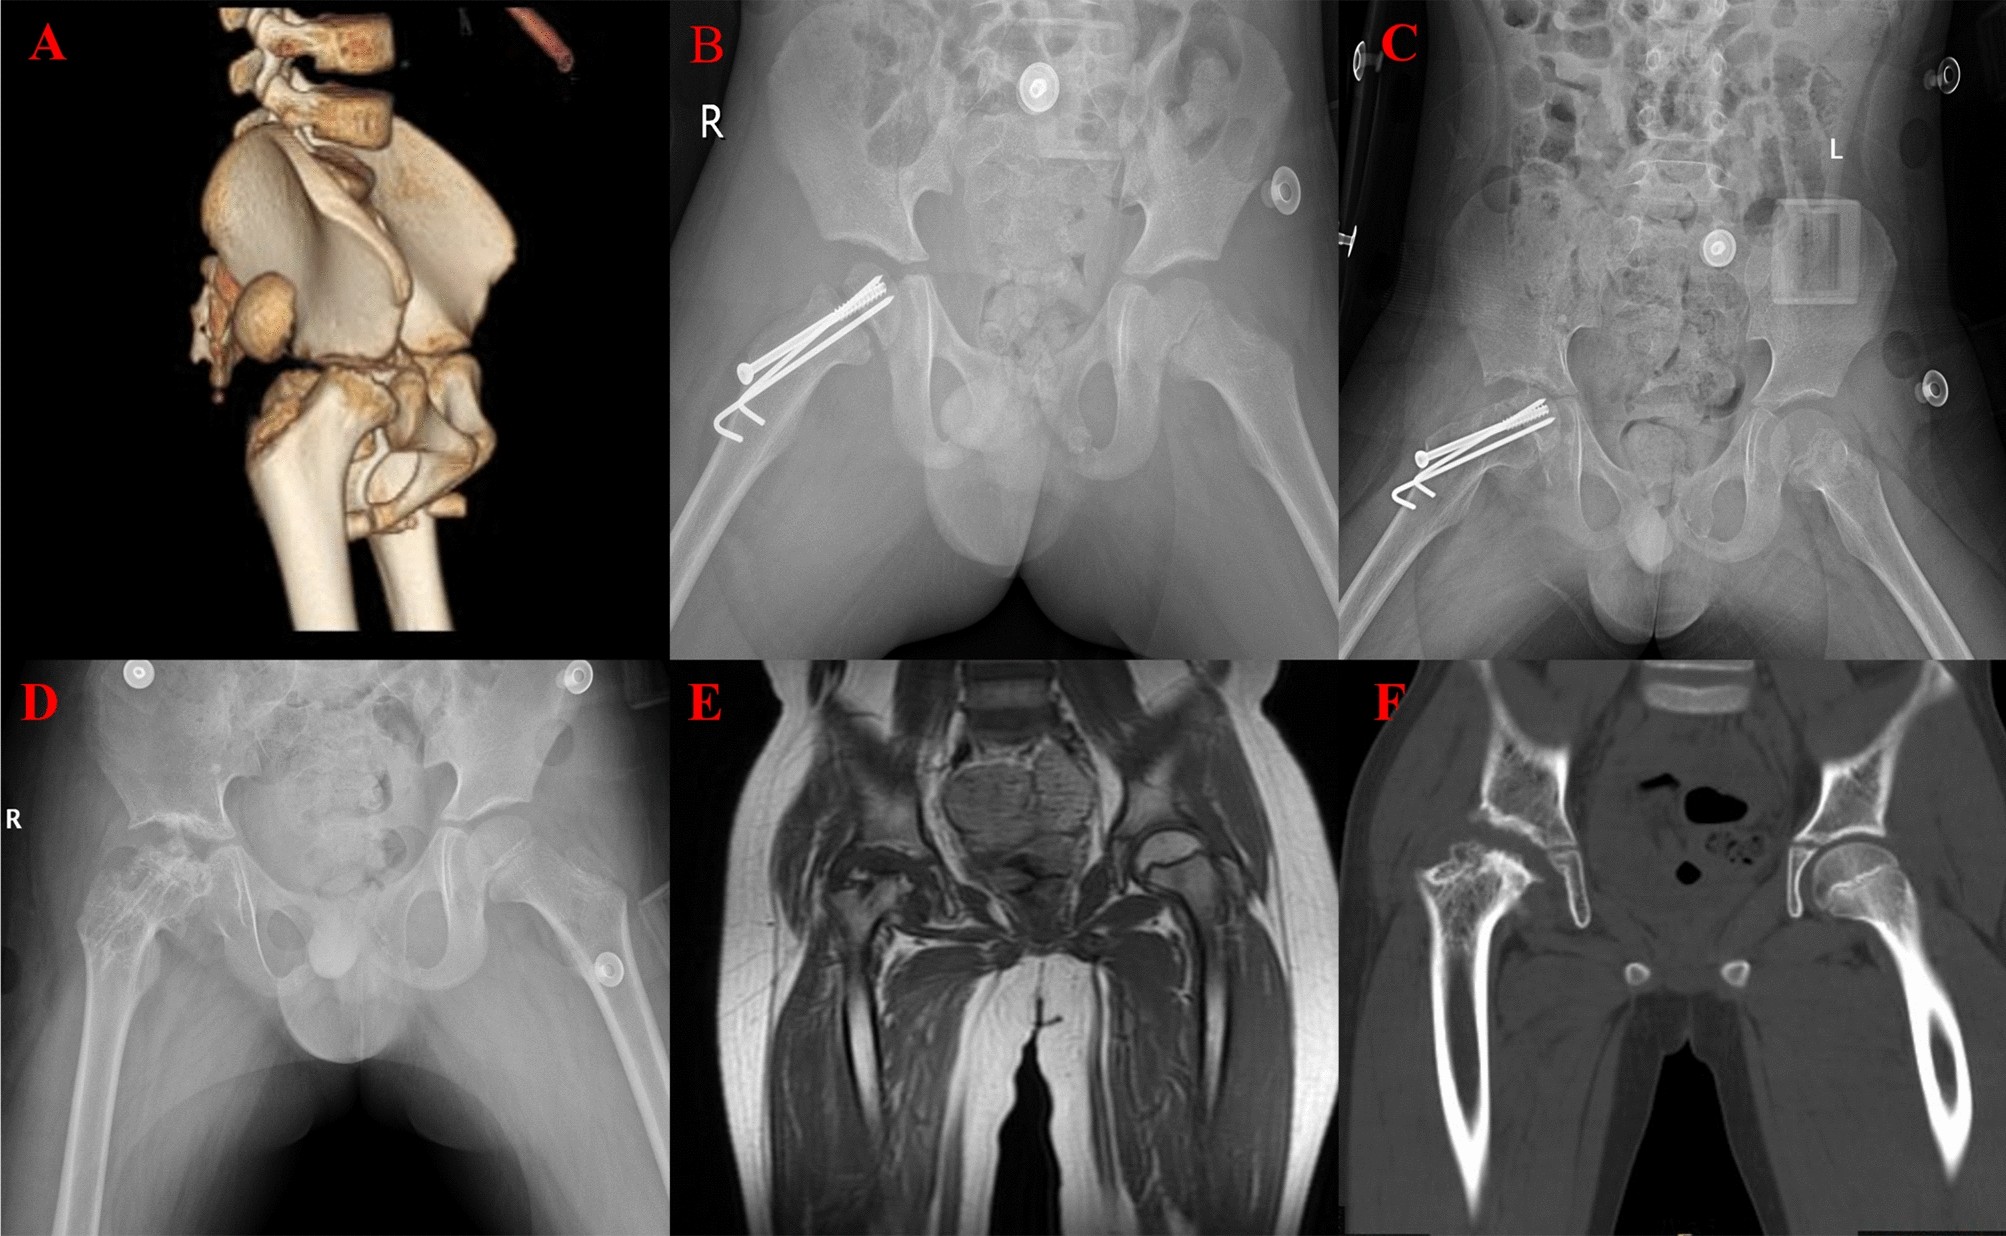

Çocuklarda kalça çıkığı, özellikle yeni doğan bebeklerde yaygın olarak görülen ortopedik bir durumdur. Kalça ekleminde femur başının (uyluk kemiği başı) kalça yuvasına tam oturmaması durumu, kalça çıkığına yol açar. Erken teşhis ve tedavi ile bu problem kontrol altına alınabilir, ancak tedavi edilmediği takdirde ciddi sağlık sorunlarına neden olabilir.

Kalça çıkığının erken teşhisi, tedavi sürecinde büyük önem taşır. Yenidoğan bebeklerde rutin kontrollerde yapılan ultrasonografi gibi görüntüleme yöntemleriyle, kalça eklemi taranarak olası anormallikler belirlenebilir. Erken teşhisle, genellikle cerrahi müdahaleye gerek kalmadan tedavi edilebilir. Pavlik bandajı gibi cihazlarla kalça eklemi stabilize edilip doğru pozisyonda tutulabilir.

Daha ileri yaşlarda veya ciddi vakalarda ise cerrahi müdahale gerekebilir. Femur başının kalça yuvasına yerleştirilmesi için yapılan cerrahi müdahaleler sonrası fizik tedavi süreci, çocuğun normal yaşantısına dönüşünü kolaylaştırır.